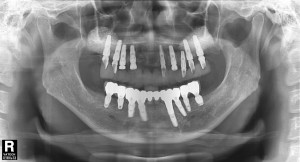

파노라마 방사선 사진도 살펴보면 치아를 잡는 치조골이 치아 뿌리 끝까지 많이 녹았음 확인할 수 있었습니다.

따라서 치아를 발치하고 전악 임플란트를 수복하기로 결정 하였습니다.